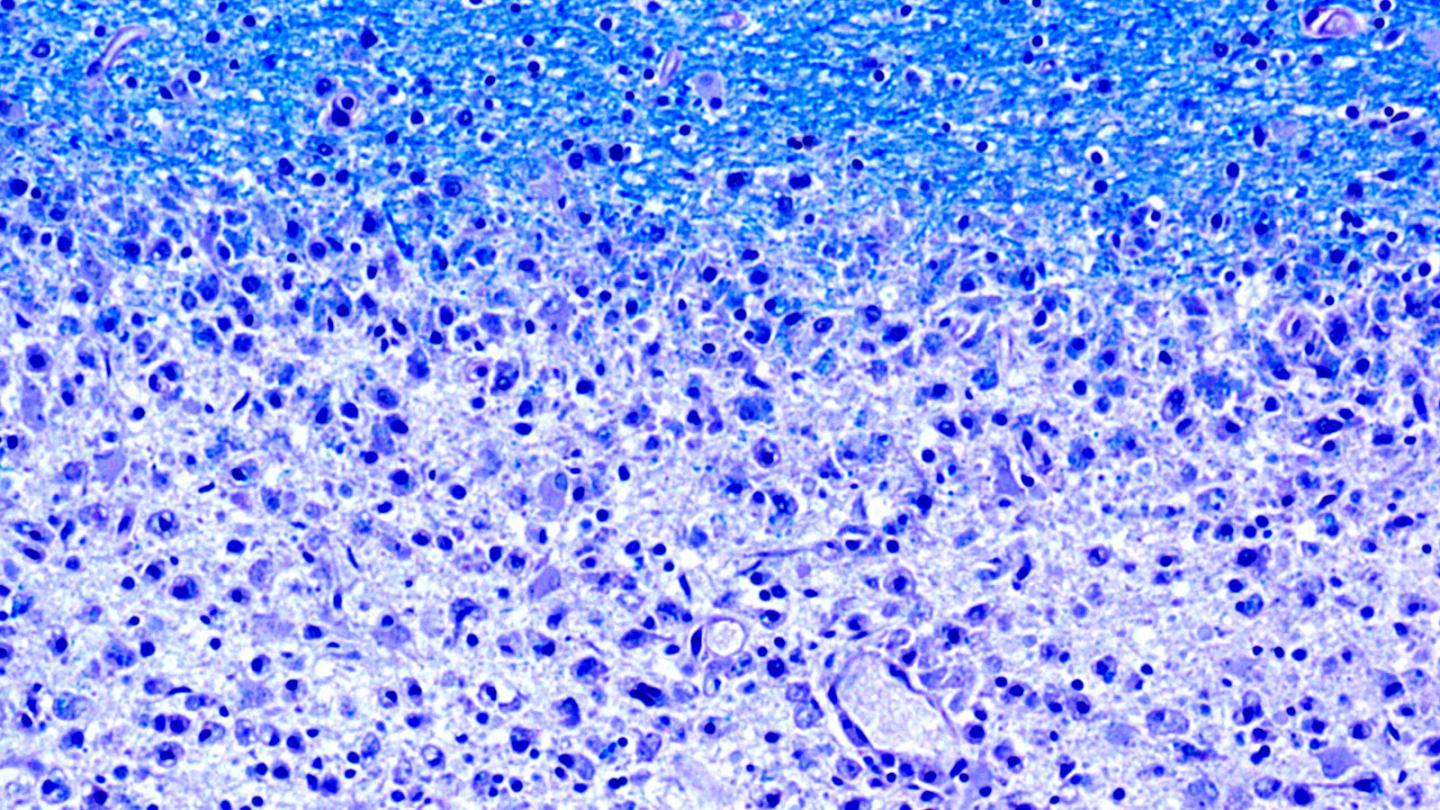

Multiple sclerosis is an autoimmune disease in which the body's own immune system attacks and damages the protective coating around nerve cells. This coating is made up of myelin - a biological membrane of protein and fatty substances - which is why research efforts to find the disease's target antigen have so far focused on the myelin membrane's components. New findings made by the research group of Mireia Sospedra and Roland Martin from the University of Zurich's Clinical Research Priority Program Multiple Sclerosis now suggest that it is worth broadening the research perspective to gain a better understanding of the pathological processes.

In the journal Science Translational Medicine , the scientists report that T cells - i.e. the immune cells responsible for pathological processes - react to a protein called GDP-L-fucose synthase. This enzyme is formed in human cells as well as in bacteria frequently found in the gastrointestinal flora of patients suffering from multiple sclerosis. "We believe that the immune cells are activated in the intestine and then migrate to the brain, where they cause an inflammatory cascade when they come across the human variant of their target antigen," says Mireia Sospedra.